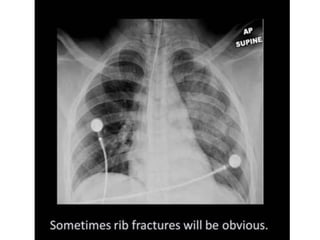

This document provides an overview of interpreting chest x-rays and identifies several key factors. It discusses the importance of inspiration, penetration, and rotation in obtaining a technically quality radiograph. It also outlines different views of chest x-rays including PA, AP, and lateral views. Finally, it identifies several anatomical structures that should be evaluated when interpreting a chest x-ray such as the lungs, heart, diaphragm, bones, and soft tissues.